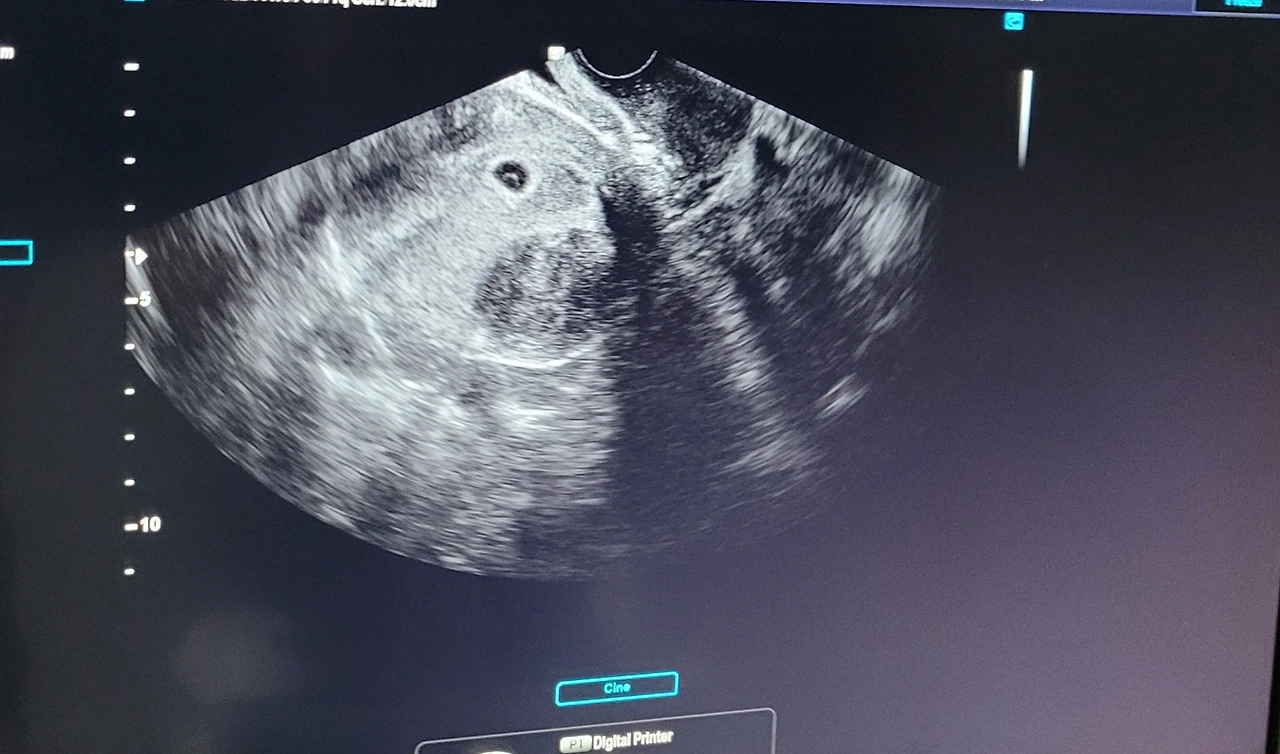

우리의 첫 만남은 계란이었다.

의사 선생님의 말에 어떻게 대답해야 하나 고민이 들었다. 영화나 드라마에서는 사람들이 울기도 하고 그런다는데... 내 감상은 그저 "오 계란~"정도였다. 아직 저 작은 녀석이 사람이 된다는 게 실감이 나지 않기도 했다. 사람으로서 그 어떤 형태도 띄지 않는 계란을 보면서 무슨 반응을 해야 할까.

초음파 사진을 보면서 떠올린 생각이 있었다. '무사히 잘 태어나서 보자'. 초음파 사진을 들고 진료실을 나오고 나서야, 나는 조금 아빠가 된다는 현실을 받아들인 것 같았다. 앞으로 저 계란이 사람이 되고 언젠가 셋이서 같이 놀 때가 오겠구나 싶었다. 아직 철없던 어른이 조금은 어른이 된 느낌이 들었다.